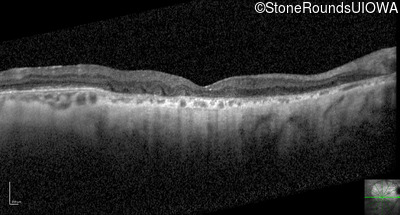

Optical Coherence Tomography - Right - 20/100 +1

Exemplar / OCT Stack